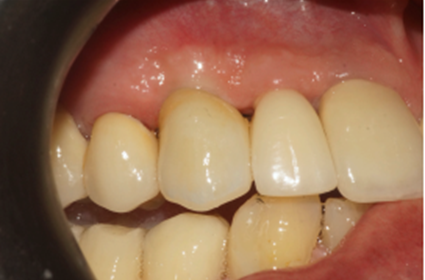

Figura 9 – Cicatrizador removido após 90 dias

Após 90 dias da instalação do implante, o cicatrizador foi removido e fazendo uso do Kit de Seleção de Componentes da mesma empresa, foi selecionado um pilar Ideale angulado de 3.3 X 4.0 X 1.5 de 17°. Essas mediadas se referem ao diâmetro, altura protética, altura do transmucoso e ao ângulo do pilar, respectivamente (Figuras 9, 10 e 11).